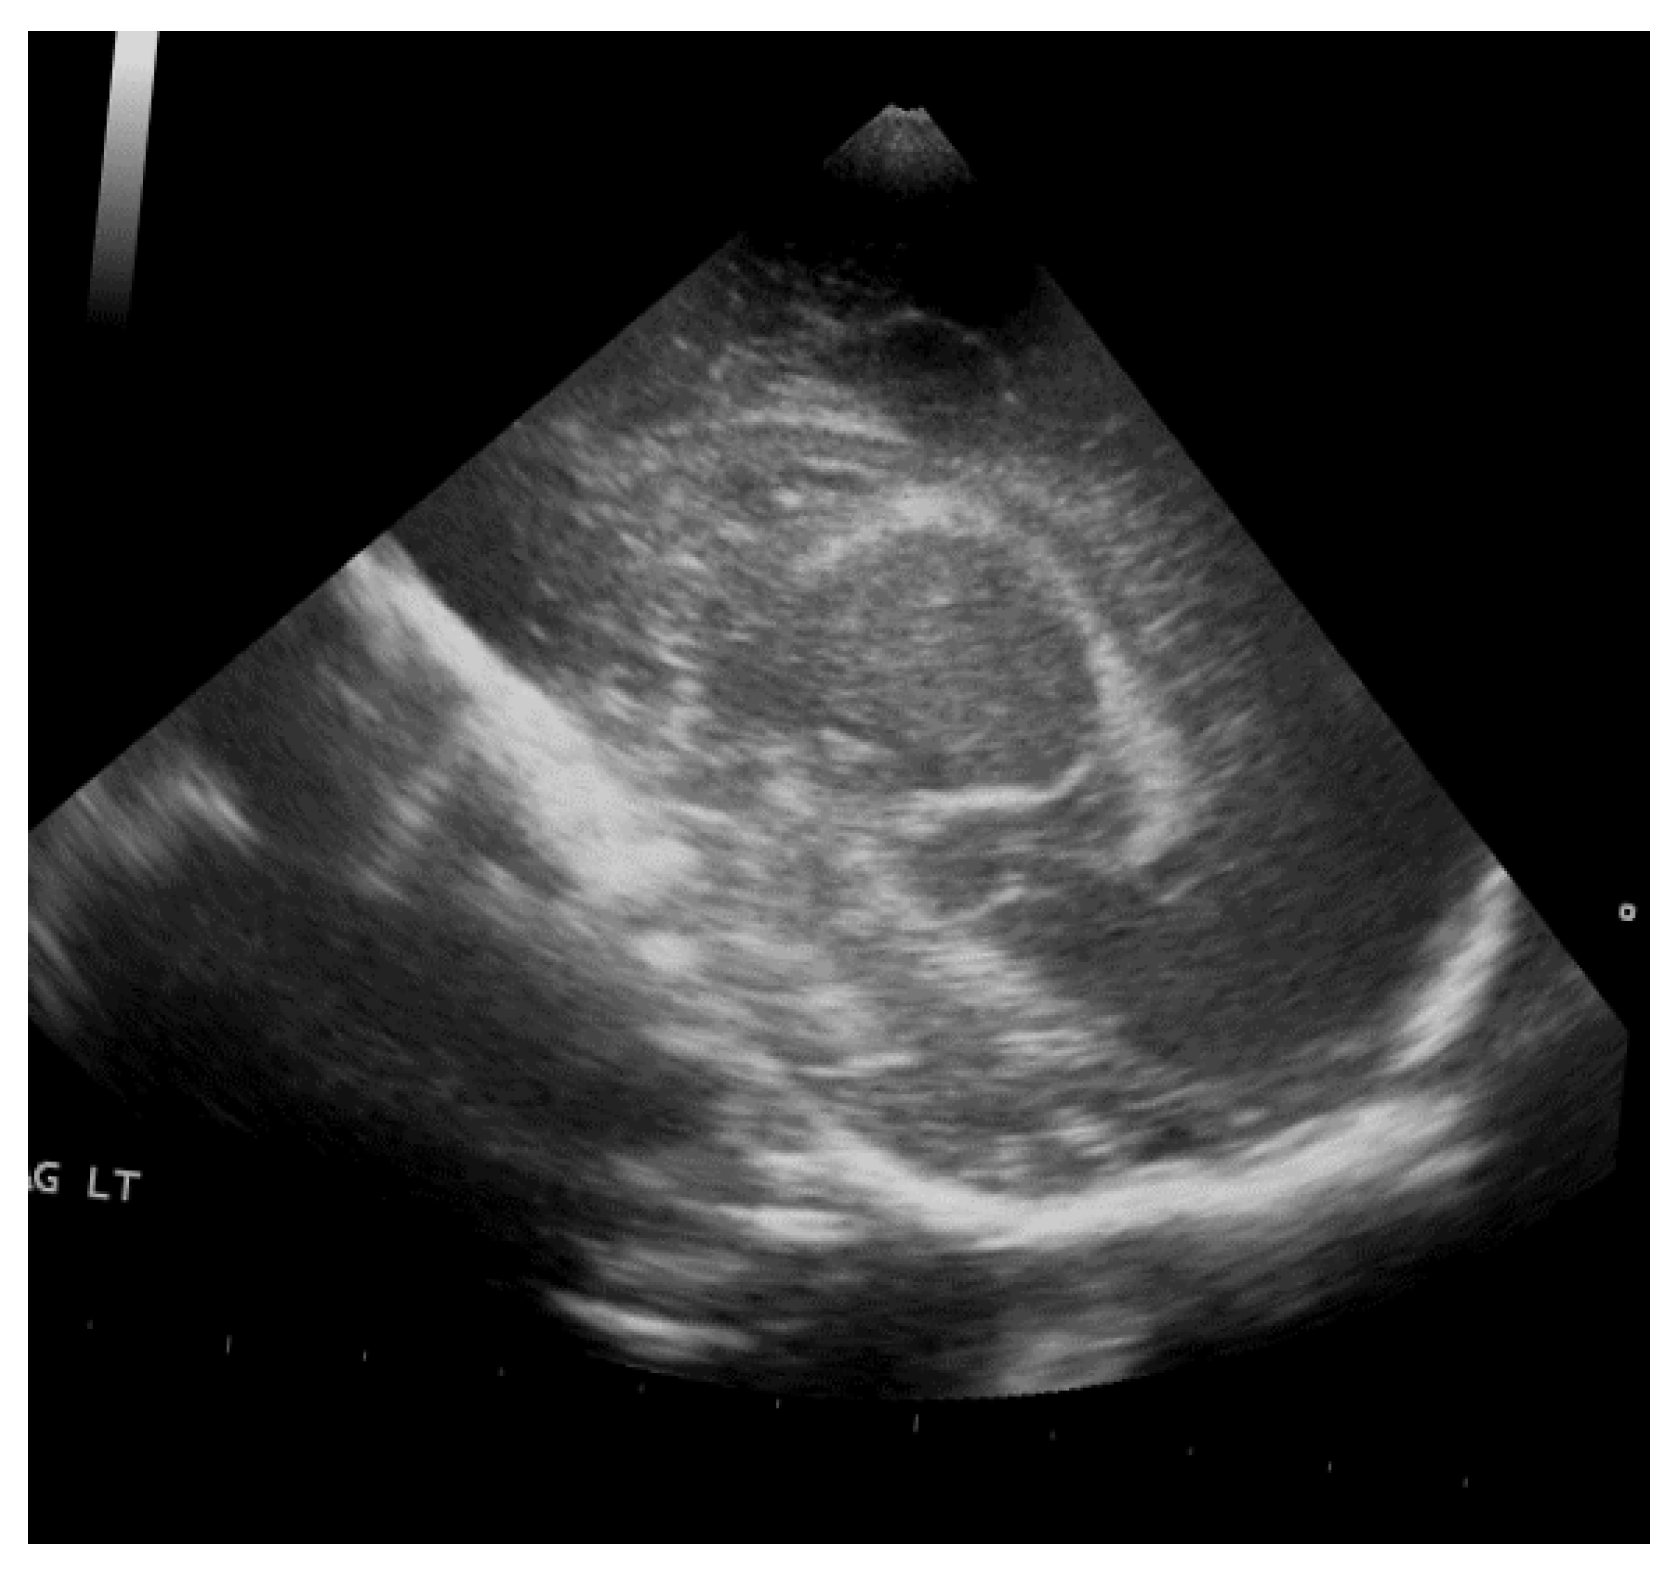

The study population comprised neonates who underwent cranial ultrasound (US) at King Fahad Hospital of the University (KFUH) in Khobar, Kingdom of Saudi Arabia. Neonatal cerebral ultrasound images were collected for this study. The inclusion criteria encompassed neonates who had undergone cranial US at KFUH, with complete sets of left sagittal, right sagittal, and coronal cranial ultrasound images, and those with confirmed diagnoses of germinal matrix hemorrhage (GMH), as shown in Figure 2. Exclusion criteria included neonates without complete sets of the required cranial US images and patients with incomplete or missing medical records. The study initially considered a total of 582 neonates who underwent cranial US, among whom approximately 40 were identified to have GMH.

Figure 2.

Sample of the dataset ((left): coronal US, (right): left US).